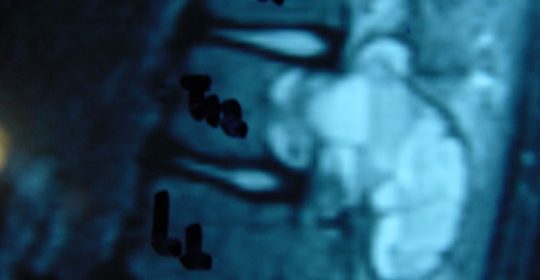

Εικ. 3: Μαγνητική τομογραφία α-στ Οβελιαία (Saggital) λήψη ακολουθία Τ1-Τ2, ζ-ιβ Εγκάρσια (Axial) λήψη ακολουθία Τ1-Τ2

Παρατηρείται ευμεγέθης εξεργασία στα οπίσθια στοιχεία του Θ12 σπονδύλου η οποία προκαλεί διόγκωση των δομών , λέπτυνση του φλοιού, χωρίς σημάδια διάσπασης του φλοιού. Η εξεργασία προβάλλει και στενεύει το σπονδυλικό σωλήνα, ενώ προκαλεί πίεση του νωτιαίου μυελού. Δεν αναγνωρίστηκαν παθολογικά ευρήματα από τον έλεγχο των σπονδυλικών σωμάτων και των μεσοσπονδύλιων τμημάτων της ΟΜΣΣ.